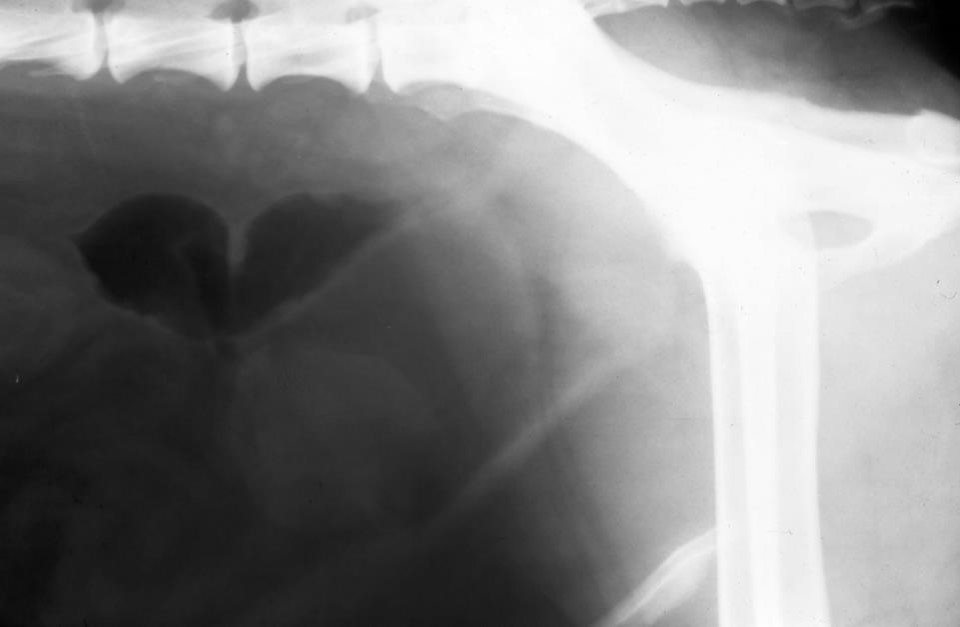

What can be seen here?

Local peritoneal dx – increase opacity

Colon – has gas in

Might be LN enlargement near colon

Inflamm vs neoplasia